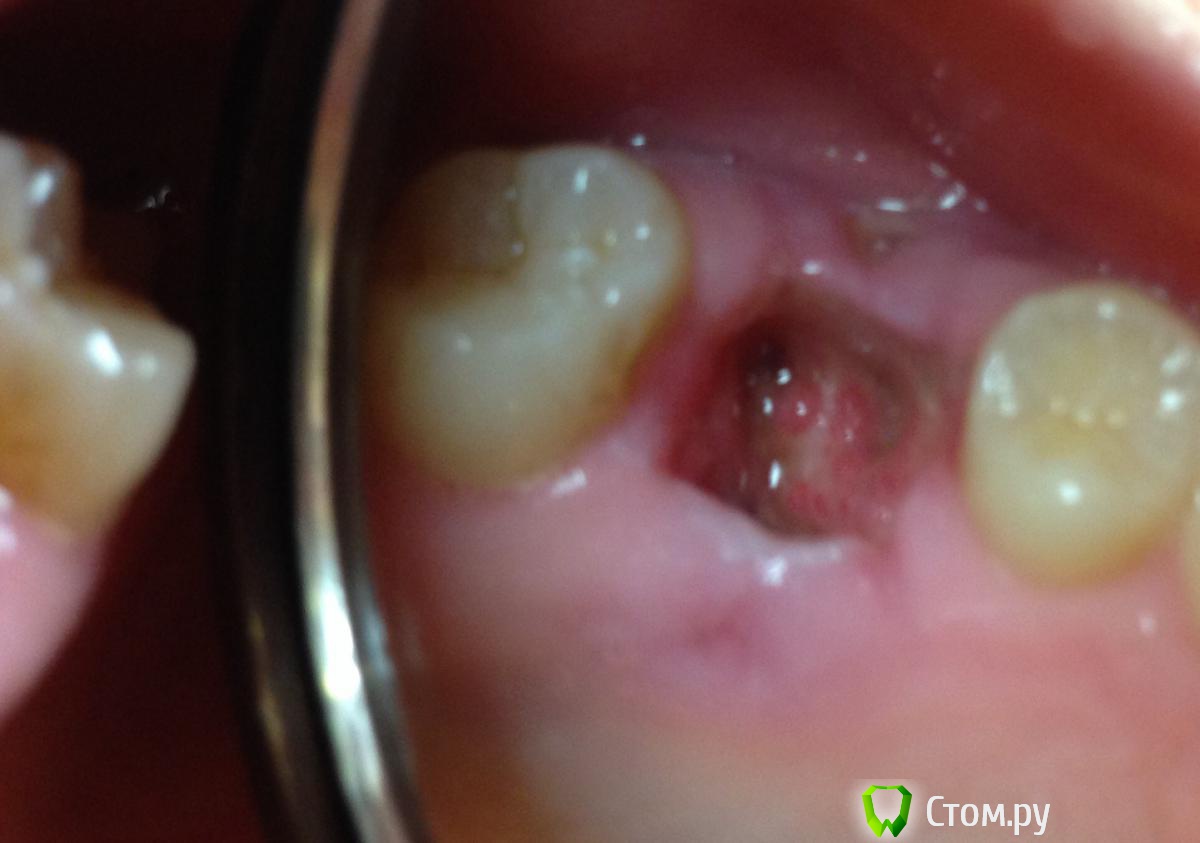

С Солкосерилом стало намного легче, ибо дырка стала просто огроменной. Замазываю ее периодически, чаще перед едой. Температура 37

8 июня - поднялась температура 37,5. Грешу на вчерашний коктейль из трубочки. Продолжаю набирать в рот Тандум Верде, замазывать дыру Солкосерилом.

С момента удаления зуба прошло 9 дней. Солкосерил уже бесит, но без него еще хуже. Еще и дырка небольшая появилась в десне после зашивания, на фото видно. Все слишком плохо? Что делать дальше? Нужны ли физио процедуры, антибиотики, что-то еще?

post-39094-0-32875400-1402226543_thumb.jpg

По Вашим фото снимкам (предварительно)  кроме  " банального"  альвеолита ничего на ум не приходит)

А как его лечить, Альвеолит? Продолжать схему Тандум Верде + Солкосерил? Как долго он обычно заживает?